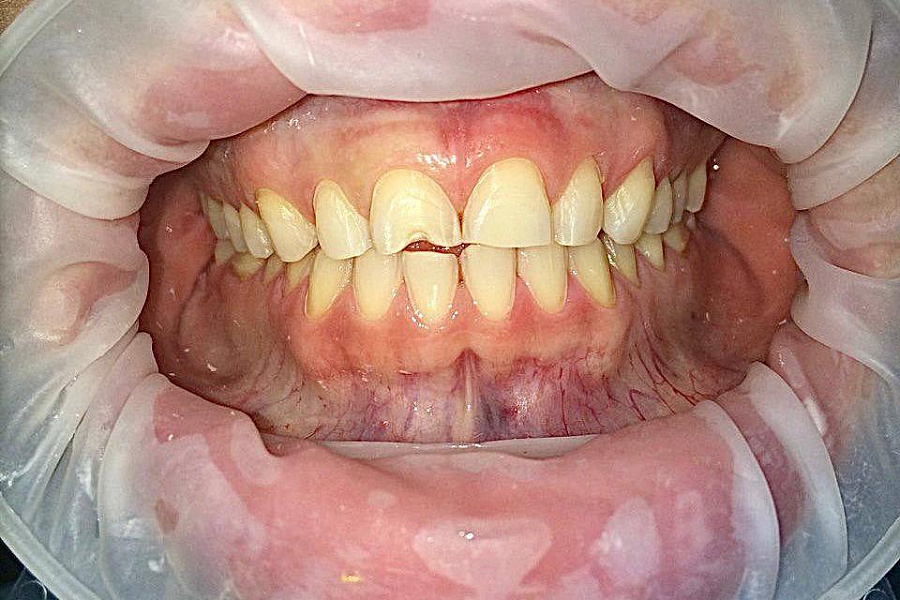

- выраженная стираемость зубов

- поврежден край переднего зуба семечками

В первую очередь был запрос на эстетическую часть. Пациентка хотела, чтобы новые зубы выглядели естественно.

Провели санацию, сделали и установили красивые натуральные виниры.

Результат на фото говорит лучше всяких слов. Пациентка очень довольна результатом!